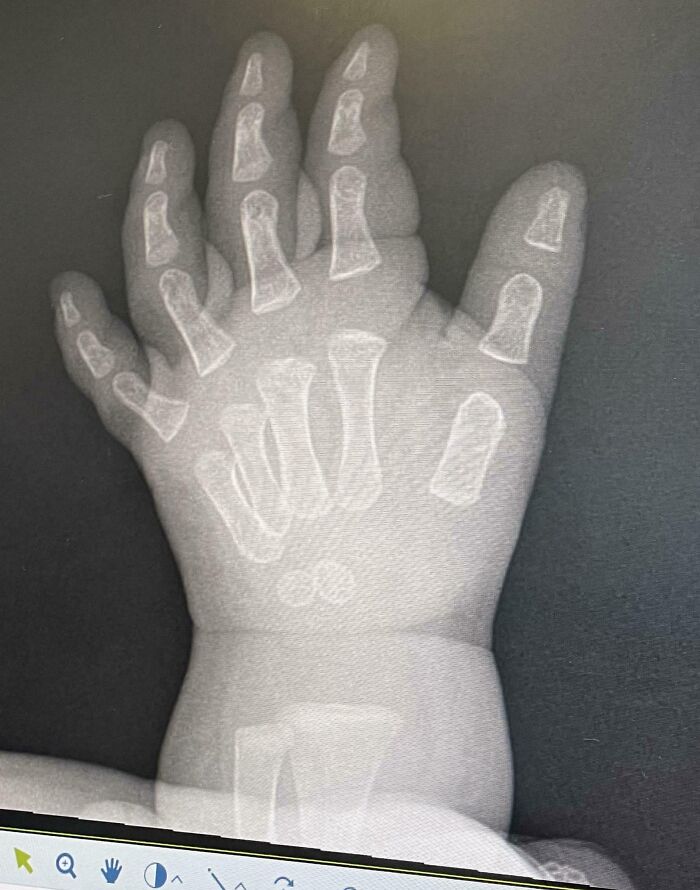

Did You Know: An X-Ray Of A Baby’s Hand Makes It Look Like Their Bones Are Just Kinda Floating Around In There

X-ray image showing a rare hand abnormality with extra fingers, highlighting surprising things about human bodies.

Our 11-month-old somehow hurt her hand/wrist, and in trying to figure out what was wrong we got some x-rays. Unfortunately nothing conclusive came from the scans, but I thought the x ray itself was mildly interesting. Baby girl is going to be fine, apparently infants have Wolverine-like regenerative powers.

Hipple Report